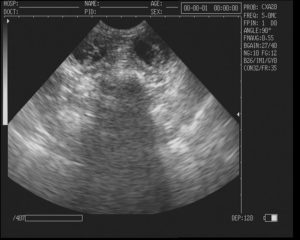

В первые недели развития эмбриона имеет смысл выполнять только трансвагинальное УЗИ.

Это обследование предполагает, что датчик вытянутой формы небольшого диаметра вводят во влагалище женщины и получают с его помощью изображение матки на мониторе аппарата.

В связи с тем, что датчик максимально приближен к изучаемой зоне, тонность исследования очень высокая. Специфической подготовки такое УЗИ не требует. Оно безопасно и не приносит осложнений.